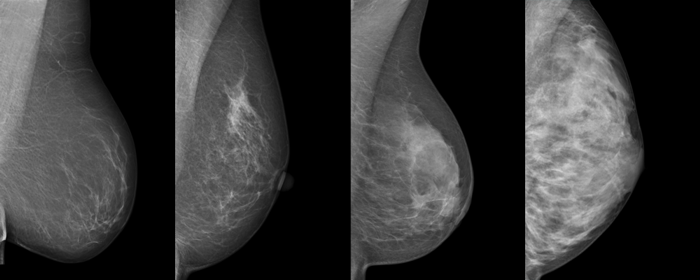

Ultraschall vs. Mammographie: Zwei Verfahren mit unterschiedlichen Stärken

Es ist wichtig zu verstehen, dass Brustultraschall und Mammographie sich nicht gegenseitig ausschließen, sondern sich ideal ergänzen. Die Mammographie ist nach wie vor das Standardverfahren für die gesetzliche Brustkrebsfrüherkennung, besonders für Frauen ab 50 Jahren, da sie sehr gut winzige Verkalkungen (Mikrokalk) darstellen kann, die ein frühes Zeichen für bestimmte Krebsarten sein können. Der Ultraschall hingegen spielt seine Stärken aus, wenn das Brustgewebe sehr dicht ist und die Mammographie dadurch an Aussagekraft verliert. Er ist zudem exzellent darin, flüssigkeitsgefüllte Hohlräume (Zysten) zu erkennen und zu beurteilen. Eine Einschränkung des Ultraschalls ist jedoch, dass er stark von der Erfahrung des Untersuchers abhängt und Mikrokalk schlechter erkennen lässt.

Wenn von "dichtem Brustgewebe" die Rede ist, meint man damit Brustgewebe, das reich an Drüsen- und Bindegewebe ist und weniger Fettgewebe enthält. Dies ist besonders häufig bei jüngeren Frauen der Fall. Das Problem bei dichtem Gewebe ist, dass sowohl Tumore als auch das dichte Gewebe selbst auf einer Mammographie hell erscheinen. Dies kann dazu führen, dass ein Tumor im dichten Gewebe quasi "maskiert" wird und schwer zu erkennen ist. Der Ultraschall umgeht dieses Problem, da er auf den Unterschieden in der Gewebestruktur basiert und Schallwellen unterschiedlich reflektiert werden. So kann der Ultraschall Tumore in dichtem Gewebe oft besser sichtbar machen, wo die Mammographie an ihre Grenzen stößt, und somit die Entdeckungsrate potenziell erhöhen.